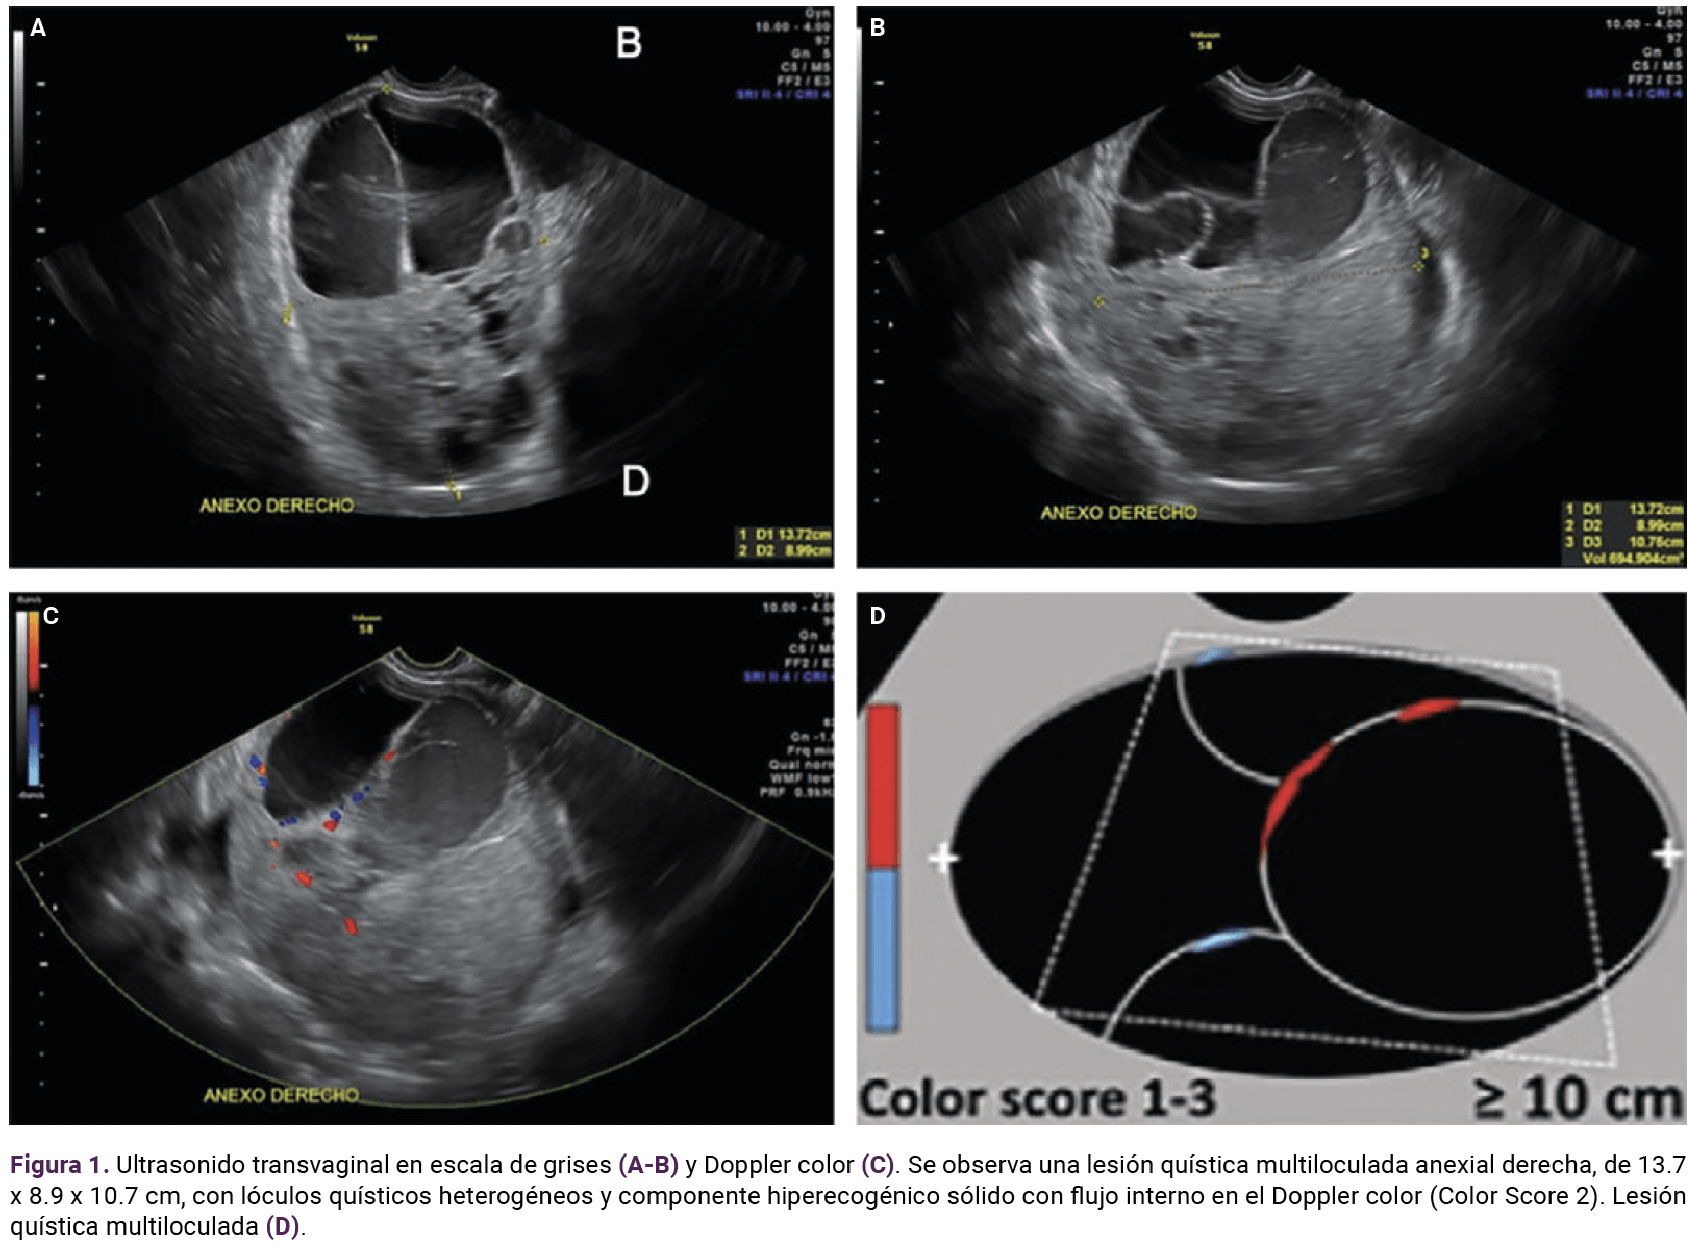

El ultrasonido pélvico reportó datos sugerentes de tumoración compleja, dependiente del ovario izquierdo (Figura 1). Se integró el diagnóstico de abdomen agudo secundario a posible torsión de quiste complejo, dependiente del ovario izquierdo. Se practicó laparotomía exploradora, donde se encontró escaso líquido libre en fondo de saco posterior. Se obtuvieron muestras del líquido y de la tumoración para estudio histopatológico. Posteriormente se procedió a la salpingooforectomía izquierda, con sangrado estimado de 50 mL. Es estudio histopatológico informó: tumor de células de la granulosa de estirpe juvenil. Figuras 2 a 4

<strong>Figura 1</strong>

Figura 1.

Puesto que el tumor de células de la granulosa es excepcional, no existen imágenes uniformes para establecer el diagnóstico. Sin embargo, de acuerdo con los estudios consultados, se encontró ecogenicidad variable entre los diferentes lóculos quísticos, uno demostraba ecos internos de bajo nivel y tabique incompleto, y el resto fueron anecoicos y tenían paredes internas lisas que componían una septación delgada regular. Por su localización e imposibilidad de visualizar el ovario ipsilateral se asumió un origen ovárico, por lo que el componente sólido se describió “heterogéneo e hiperecogénico”, rodeando el parénquima ovárico con pequeños folículos periféricos. Los septos y el componente sólido mostraron un flujo mínimo en el Doppler color (Color score 2). Con base en las características previamente descritas, se clasificó la lesión con categoría de riesgo intermedio de neoplasia maligna O-RADS 4.21,22